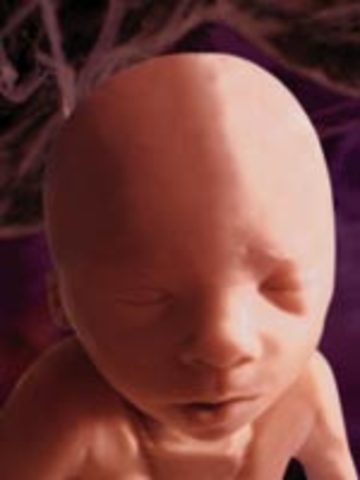

• Week 12: Fingernails and Toenails Appear

Week 12: Fingernails and Toenails Appear

The fetus is beginning to move a lot more. The face is also beginning to look a lot more like a baby's face. The pancreas is beginning to function.